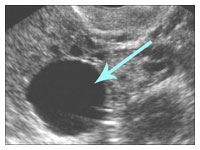

Не стоит игнорировать такие сигналы: на яичнике могла появиться киста, которая нарушает его работу. Врач легко обнаружит ее во время гинекологического осмотра, а УЗИ поможет установить, насколько велика киста, где она находится и является ли необходимым ее удаление кисты яичника. Операцию следует проводить в том случае, если киста не поддается консервативному лечению или если есть подозрения, что со временем перерасти в злокачественную опухоль яичника.